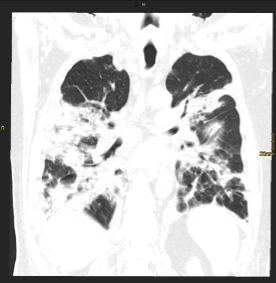

Pressebilder frei zum Download: ©Univ.-Klinik für Radiologie Innsbruck

BU: CT Thorax eines Teilnehmers während des stationären Aufenthalts (Bild links) und nach einem Jahr (Bild rechts) im Vergleich. Die initial ausgeprägten Gewebsvermehrungen sind deutlich rückläufig, jedoch zeigen sich residuell noch feine lineare Verdichtungen in beiden Unterlappen.